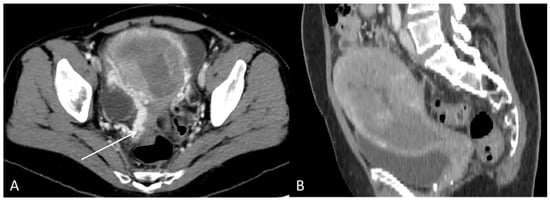

Figure 7. The CT with contrast enhancement performed after approximately two months of sorafenib treatment showed a morphological progression of the primary tumour in the uterus. During this time, the patient had also received radiation therapy (3Gyx10) of the uterus as palliative treatment due to heavy vaginal bleeding. (A) Axial CT and (B) sagittal CT showed tumour masses in the uterine cavity with patchy hypodensities consistent with necrosis. In the tumour periphery, contrast-enhanced varicose veins were visible, consistent with pelvic congestion syndrome ((A), arrow).